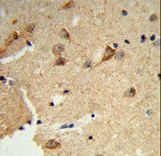

- Experimental details

- Formalin-fixed and paraffin-embedded human brain tissue reacted with DTX4 Antibody , which was peroxidase-conjugated to the secondary antibody, followed by DAB staining. This data demonstrates the use of this antibody for immunohistochemistry; clinical relevance has not been evaluated.